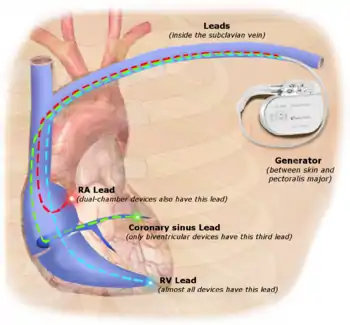

Permanent transvenous pacing

Permanent pacing with an implantable pacemaker involves transvenous placement of one or more pacing electrodes within a chamber, or chambers, of the heart, while the pacemaker is implanted under the skin below the clavicle. The procedure is performed by incision of a suitable vein into which the electrode lead is inserted and passed along the vein, through the valve of the heart, until positioned in the chamber. The procedure is facilitated by fluoroscopy which enables the physician to view the passage of the electrode lead. After satisfactory lodgement of the electrode is confirmed, the opposite end of the electrode lead is connected to the pacemaker generator.

- Single-chamber pacemaker. In this type, only one pacing lead is placed into a chamber of the heart, either the atrium or the ventricle.[10]

- Dual-chamber pacemaker. Here, wires are placed in two chambers of the heart. One lead paces the atrium and one paces the ventricle. This type more closely resembles the natural pacing of the heart by assisting the heart in coordinating the function between the atria and ventricles.[10]

- Biventricular pacemaker. This pacemaker has three wires placed in three chambers of the heart. One in the atrium and two in either ventricle. It is more complicated to implant.[10]

The pacemaker generator is a hermetically sealed device containing a power source, usually a lithium battery, a sensing amplifier which processes the electrical manifestation of naturally occurring heart beats as sensed by the heart electrodes, the computer logic for the pacemaker and the output circuitry which delivers the pacing impulse to the electrodes.

Most commonly, the generator is placed below the subcutaneous fat of the chest wall, above the muscles and bones of the chest. However, the placement may vary on a case-by-case basis.

CRT devices have at least two leads, one passing through the vena cava and the right atrium into the right ventricle to stimulate the septum, and another passing through the vena cava and the right atrium and inserted through the coronary sinus to pace the epicardial wall of the left ventricle. Often, for patients in normal sinus rhythm, there is also a lead in the right atrium to facilitate synchrony with the atrial contraction. Thus, the timing between the atrial and ventricular contractions, as well as between the septal and lateral walls of the left ventricle can be adjusted to achieve optimal cardiac function.

A pacemaker may be implanted whilst a person is awake using local anesthetic to numb the skin with or without sedation, or asleep using a general anesthetic.[25] An antibiotic is usually given to reduce the risk of infection.[25] Pacemakers are generally implanted in the front of the chest in the region of the left or right shoulder. The skin is prepared by clipping or shaving any hair over the implant site before cleaning the skin with a disinfectant such as chlorhexidine. An incision is made below the collar bone and a space or pocket is created under the skin to house the pacemaker generator. This pocket is usually created just above the pectoralis major muscle (prepectoral), but in some cases the device may be inserted beneath the muscle (submuscular).[26] The lead or leads are fed into the heart through a large vein guided by X-ray imaging (fluoroscopy). The tips of the leads may be positioned within the right ventricle, the right atrium, or the coronary sinus, depending on the type of pacemaker required.[25] Surgery is typically completed within 30 to 90 minutes. Following implantation, the surgical wound should be kept clean and dry until it has healed. Some movements of the shoulder within a few weeks of insertion carry a risk of dislodging the pacemaker leads.[25]